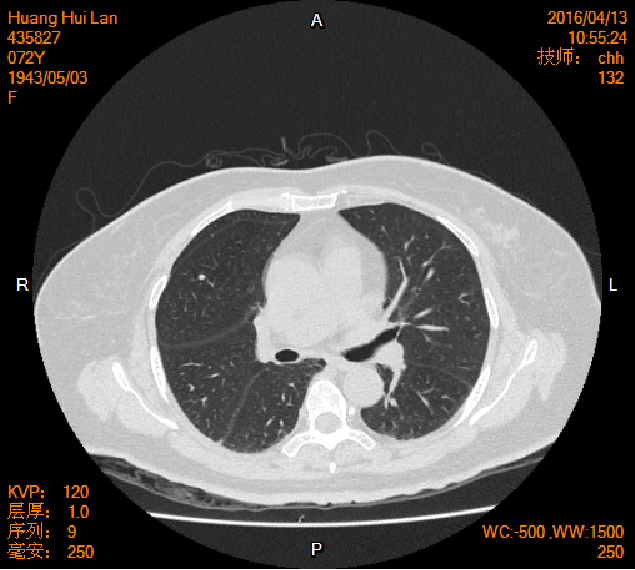

2016-04-13胸腹盆CT